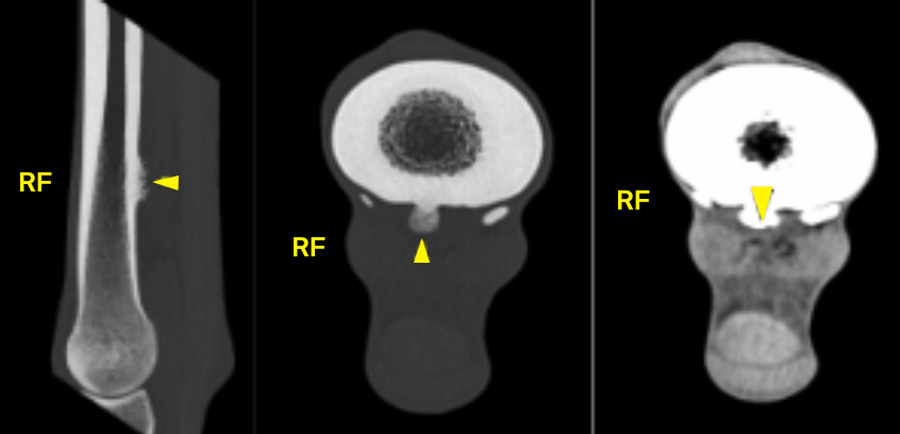

Computed tomography

Computed tomography (CT) provides the greatest diagnostic accuracy. CT reconstruction clearly demonstrates the position of the spike, the presence of synovial effusion, and any associated tendon damage. Flexed, non‑weightbearing images may allow tears in the epitenon to open when not under tension, while seeing the spike protruding into the body of the DDFT on a weightbearing image is diagnostic. When available, CT with intra‑thecal contrast is ideal, particularly for surgical planning.

In many cases, CT also helps clarify the extent of tendon involvement, especially when conventional imaging has been inconclusive.

Damage to the DDFT may also be apparent, particularly with flexed, non-weightbearing images allowing tears in the epitenon to open when not under tension. Seeing the spike protruding into the body of the DDFT on a weightbearing image is diagnostic.

If available, CT of the carpal sheath, ideally with intra-thecal contrast, will provide the most accurate diagnostic information, helping guide surgical planning as well as predicting prognosis in the presence of concurrent injury to the region.